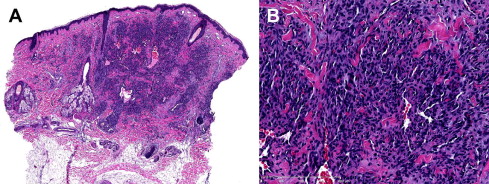

WT1 immunostaining has been used to discriminate between vascular neoplasms and most vascular malformations. A study by Lawley and colleagues showed WT1 expression in infantile hemangiomas (8 of 9), pyogenic granulomas (2 of 2), angiosarcomas (9 of 9), epithelioid hemangioendothelioma (1 of 1), and hobnail hemangiomas (1 of 1). A single case of malignant hemangioendothelioma was negative for WT1. However, vascular malformations (2 port-wine stains, 10 venous malformations, and 8 lymphatic malformations) did not show any positive endothelial staining. More recently Trindade and colleagues, confirmed these results and expanded these findings. They found expression of WT1 in arteriovenous malformations (AVMs), noninvoluting congenital hemangiomas (NICHs) ( Fig. 1 A and B), rapidly involuting congenital hemangiomas (RICHs), tufted angiomas, and spindle cell hemangiomas. They also confirmed the absence of WT1 expression in anomalous vessels in capillary, lymphatic, and venous malformations. All AVMs showed positivity for WT1 in the lesional endothelia; this could be related to the proliferative stage of the AVM, because all their cases were in stage II, with arteriovenous shuntings and clinical enlargement.

These vascular proliferations differ from IH in their growth patterns and lack of immunoreactivity for the glucose transporter-1 protein (GLUT1), which is a sensitive and specific marker for IH (see Fig. 1 B). This protein is not detectable in the blood vessels of normal skin or in most other types of vascular tumors but is highly expressed in endothelia at sites of blood-tissue barriers, which include the brain and placenta.